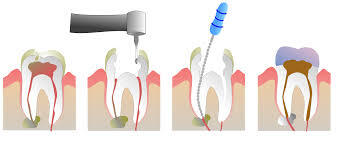

Endodoncia

Endodoncia (Tratamiento de conductos o canal radicular) Blanqueamiento de dientes endodonciados